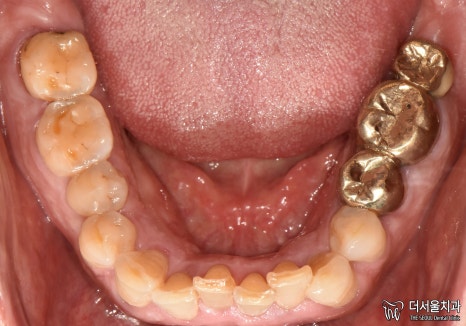

1. 구강 체크

서현역 치과를 찾아오셨던 환자분은

앞니와 왼쪽 끝 어금니에

이상 증세를 느껴 찾아오셨습니다.

겉으로 봤을 때는 큰 문제는 없는 것처럼 보입니다.